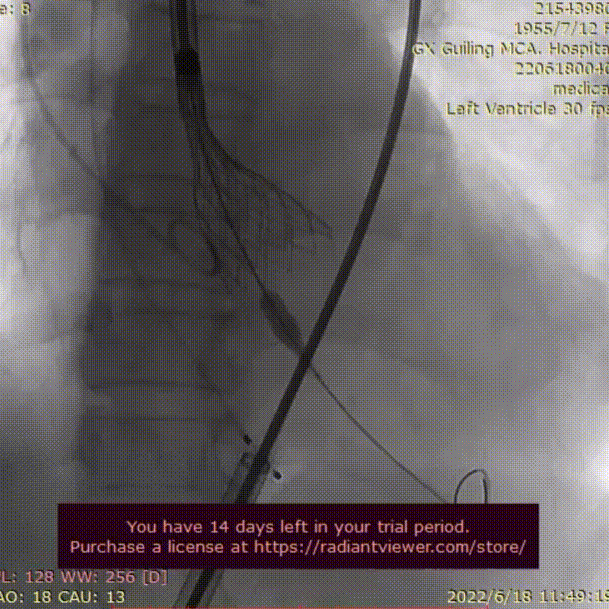

主动脉根部造影

23mm球囊预扩

AV29瓣膜定位

AV29瓣膜释放到工作位

AV29瓣膜回收调整后定位

AV29瓣膜再次释放到工作位

AV29瓣膜释放后造影,形态良好

术后血管造影,无血管损伤

本例手术为中度钙化三叶式病变中度主动脉瓣狭窄并重度关闭不全TAVR手术,外周入路走行迂曲,散在钙化,预估术中入路穿刺难度较大,存在入路血管损伤及相关并发症风险,术前手术团队对患者进行了全面细致的评估,确定假体瓣膜锚定区域范围,制定术前释放策略,入路穿刺规范操作,小心通过,避免了入路血管损伤及相关并发症。王海永主任团队通力配合、精准释放,充分利用TaurusElite可回收功能,在瓣膜释放至2/3时,多角度评估瓣膜植入深度、锚定力以及冠脉灌注情况,确认瓣膜植入深度合适、锚定力稳定,缓慢逐个脱钩,进行瓣膜释放,瓣膜释放后造影显示瓣膜膨胀良好,无明显瓣周漏,手术圆满完成。